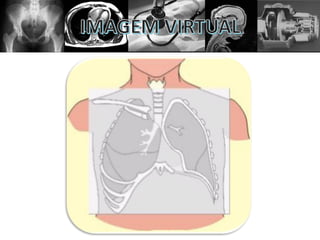

A imagem pode ser:

1- Virtual;

2- Radiante;

3- Luminosa;

4- Latente;

5- Radiográfica.

Imagem virtual